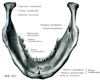

3. 顎関節